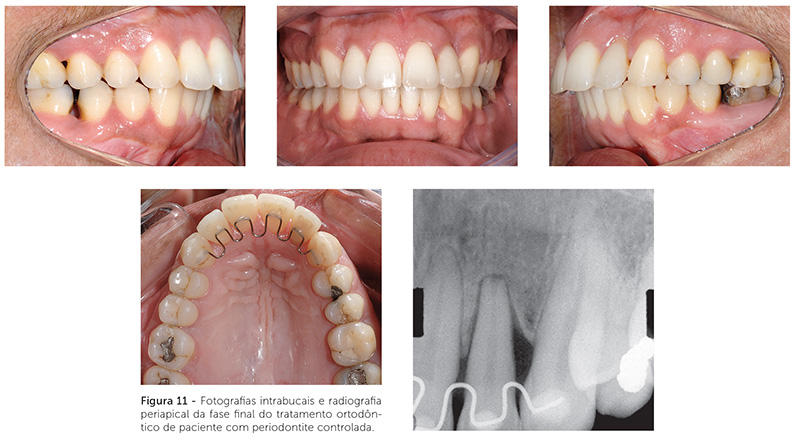

O tratamento ortodôntico de um paciente com doença periodontal não pode ser visto como um tratamento comum. Todos os casos ortodônticos exigem diagnóstico e planejamento efetivos, mas, em um paciente periodontal, esse exercício torna-se mais difícil. Deve-se ter em mente que todo tratamento deve beneficiar o paciente. Quando o periodonto está comprometido e há um planejamento ortodôntico falho, a chance do paciente ser prejudicado por um tratamento mal conduzido é grande. Por isso, esses casos exigem integração, de modo que o paciente não deve iniciar a movimentação ortodôntica sem a aprovação do periodontista, e esse deve acompanhar a situação periodontal durante todo o tratamento ortodôntico25,26. Um exemplo de movimentação dentária em paciente com pouca inserção periodontal pode ser visto nas Figuras 9, 10 e 11.

O tratamento ortodôntico de pacientes com doença periodontal controlada é, muitas vezes, um tratamento mais curto e direcionado. A redução do periodonto de suporte gera importantes implicações para o movimento dentário ortodôntico. Existe uma relação linear direta entre o suporte alveolar e a localização do centro de resistência. Conforme o osso alveolar de suporte vai sendo reduzido, o centro de resistência vai se movendo apicalmente. A intensidade e o ponto de aplicação de força durante o tratamento ortodôntico devem ser adaptados em tais situações. As forças utilizadas devem ser de magnitudes menores que aquelas utilizadas em periodontos saudáveis. Para que o movimento dentário seja mais controlado — haja vista que o centro de resistência encontra-se localizado mais apicalmente —, a colagem dos acessórios pode ser realizada mais gengivalmente.